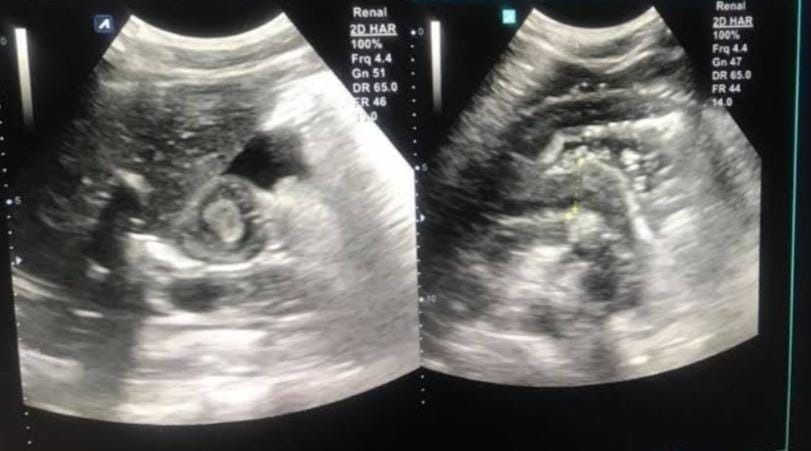

Rahaf is a 7-year-old girl from Egypt, full of life and dreams, but now she is fighting a battle no child should ever face—stomach cancer. Her pain is unbearable, and her treatment is expensive, putting an overwhelming burden on her single mother, who is struggling to keep her alive.

Rahaf was once a cheerful and playful child, but now she can barely eat without pain. She has lost weight rapidly, and every day is filled with discomfort. She often asks her mother, “When will I feel better?” but there is no answer—only the fear of what will happen if she doesn’t get the treatment she needs.

To make things worse, Rahaf’s twin sister has started showing symptoms, but her mother cannot afford a medical checkup to see if she is also sick. Their father was in a car accident three years ago, leaving him completely disabled with no source of income.